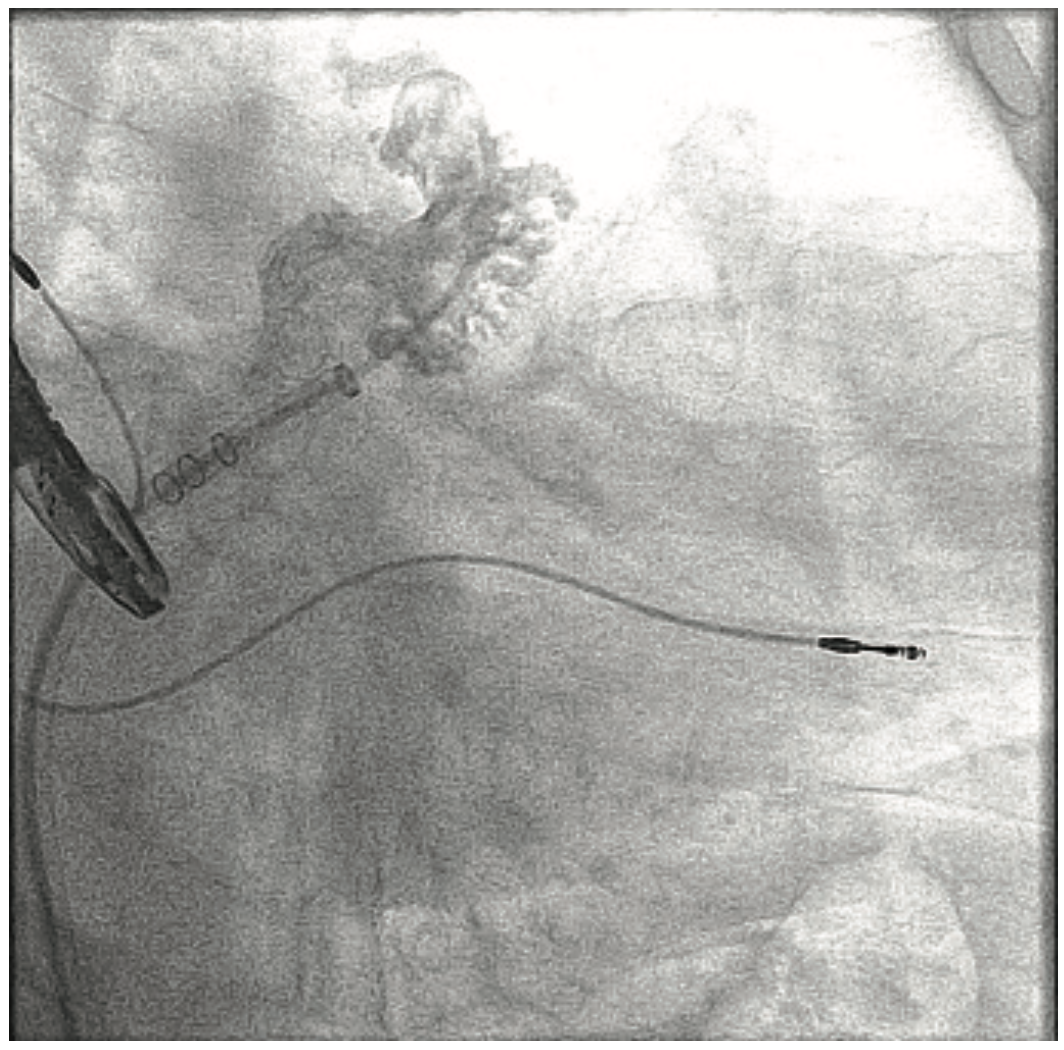

For mitral valve procedures, we use the ACIST to determine the mitral annular plane. It definitely requires high-flow injections, because there is a lot of volume going through the mitral valve. You also have to switch from doing a left atrial angiogram, which requires maybe 10 ccs of contrast, to doing a left ventriculogram, which requires maybe 10-20 ccs of contrast. The ACIST permits us to move between those injections quickly. If you are trying to characterize the left or right atrium in a transseptal procedure, it can easily be done with the ACIST. Another advantage of the ACIST is that because it offers higher and more consistent flow than with a hand injection, I can keep my small catheter in place and still get an optimal result. We also use the ACIST for left atrial appendage closures (Image 1). Using pre-procedural CT scans, the Philips system allows you to overlay your CT images onto the fluoroscopic image. Using an ACIST contrast injection hooked up to the Philips system, you can also do a rotational angiogram to generate a 3D image. We have also used the ACIST for pulmonary angiograms (Images 2-3) and pulmonary stenting. The images show a case of a patient who presented with acute chest pain. We were able to image his coronaries and when these proved to be normal, we performed a pulmonary angiogram in the same setting. For pulmonary valve stenting, you definitely need a contrast injection in the right ventricular outflow tract to make sure you have the necessary size and space. If you do a coarct stent as well, you want a high-flow injection to characterize the anatomy. I was involved in stem cell studies a few years ago, and in determining the sites for injection, we would perform a left ventriculogram to characterize where we want to inject cells, and quickly move to a coronary injection to guide our injections, without having to change the system between angiograms.

This is a 79-year-old woman with emphysema, arthritis, and severe aortic stenosis, and she needed a TAVR. There were several issues with her TAVR: one was that her coronary heights were low. If you put a TAVR valve in a patient with very low coronary heights, there is a chance that the native valve will get pushed up and occlude the coronary artery. We’ve had that happen once before, and the patient died from it, so it is a very serious complication. We did a novel procedure called the bioprosthetic aortic scallop intentional laceration to prevent iatrogenic coronary artery obstruction (BASILICA) procedure, where you slice the leaflet of the native aortic valve in half. Even though the leaflet gets pushed up, since it has been sliced in half, it won’t occlude the coronary artery. We first needed to look at her coronary arteries and the cusps using 3-6 cc coronary injections, and then we performed the BASILICA procedure. The patient also had an anomalous takeoff of her carotid arteries. We wanted to use a carotid embolic protection device, but because she had such an anomalous takeoff, it had to be placed in a very unique way. We did have a CT scan and had to correlate it with the patient so we would know exactly where to put the device. We needed to take an arch angiogram, which is a higher power contrast injection, 10 for 15 ccs or 10 for 20 ccs. The TAVR procedure was done as usual, using the 10 cc contrast injection I described earlier, to measure the annulus planes and look at implant depth. Then we looked at the coronary arteries, because it turned out that the patient needed a stent in her coronary artery. At the end of the case, we wanted to make sure that our closure of the large-bore access sheath was sufficient, so we flipped down to the leg and took a picture there using digital subtraction angiography and a 2 cc injection. I’ll share a second case that also demonstrates the versatility of the ACIST (Images 2-6). This was a patient with acute shortness of breath and chest pain, and there was a question of whether he was having a pulmonary embolus or a heart attack. The electrocardiogram was unclear. We took him back to the lab and were able to do a pulmonary angiogram, then visualize the coronaries, all on one setting. We also did an iliac angiogram, because we used that access in order to give him a support device. This case required pulmonary (Images 2-3), coronary (Images 4-5), and iliac angiograms (Image 6), all done with use of the ACIST CVi system.